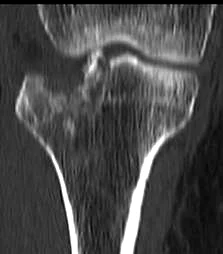

Advanced Imaging

- CT Scan:

- In complex and intra-articular fractures

- In spine

- In pelvic and acetabular fractures

- In calcaneal fractures